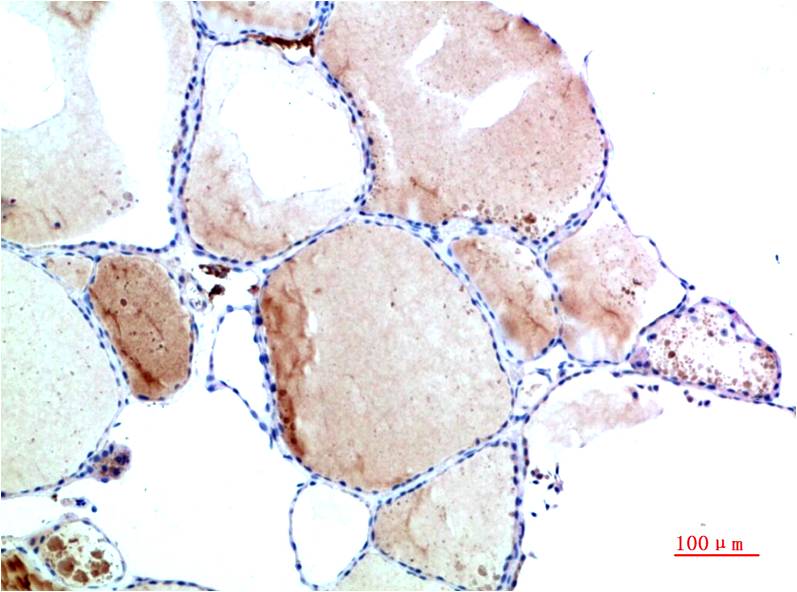

TTR Mouse Monoclonal Antibody(9B5)

Catalog NO.:BE3690

Applications :WB, IHC

Reactivity :H

Recommended dilutions: WB 1:1,000-2,000 IHC 1:100-200

Specificity: The TTR Mouse Monoclonal Antibody can detects endogenous TTR proteins.